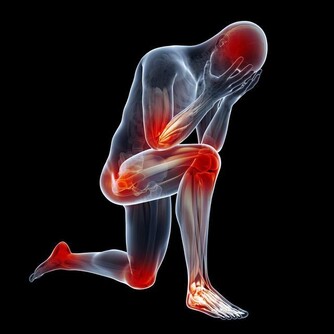

三、按摩太衝穴

太衝穴是肝經的原穴,常常按摩,可以起到疏通經絡,疏肝理氣等保健作用。

按揉時力度控制在略微感到疼痛就可以,切忌用力過大引起皮下淤血。

每次按壓的時間連續4~5分鐘即可了,按摩結束後喝適度的水有利於加速人體內部的代謝。